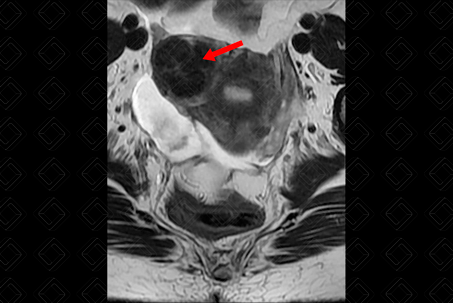

Descrição das figuras 1, 2, 3 e 4: Ressonância magnética da pelve feminina. Imagens pesadas em T2 nos planos axial e sagital (A = bexiga; B = útero; C = reto). Útero em retroversão, de contorno lobulado e sinal heterogêneo, por conta de nódulos miometriais, bem delimitados, hipointensos em T2, compatíveis com leiomiomas, destacando-se:

• Transmural, corporal posterior, medindo 5,0 x 4,8 x 4,6 cm (setas vermelhas à direita);

• Subseroso, corporal lateral direito, medindo 3,0 x 2,0 x 1,8 cm (setas vermelhas à esquerda).